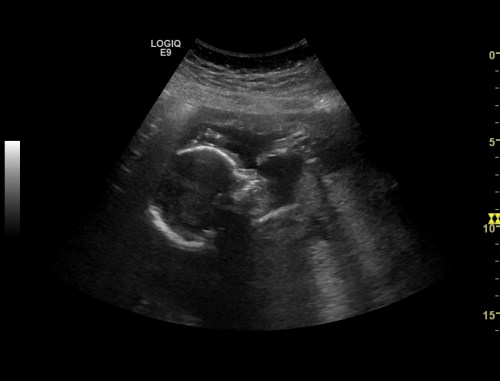

Number three

Baby number three is gonna be a boy!! We found out last week at my Week 20 ultrasound. We are super excited and a little scared to find out what having a boy is all about. But we are so thankful for this special gift.